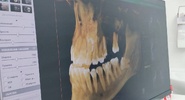

Общественники потребовали контроля за стоматологическими клиниками в Петербурге

Петербург занял первое место в антирейтинге российских регионов по количеству нелегальных стоматологических клиник.Neva.Today

В городе на Неве порядка 80% стоматологий работают нелегально или с нарушениями закона.Петербургский дневник